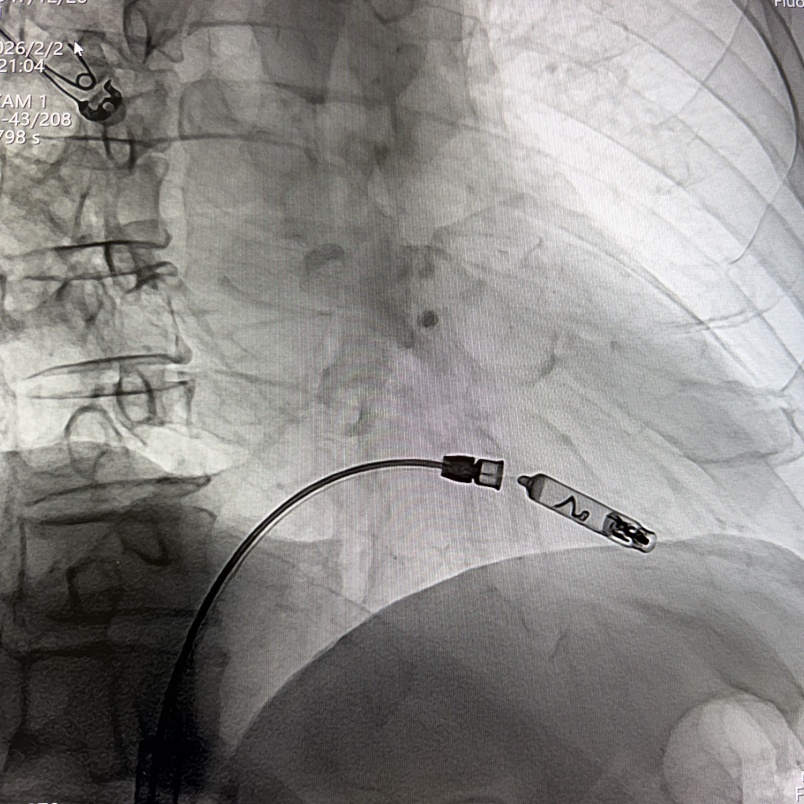

RAO 30°体位下,缓慢推送导管,直至保护套筒位于右心耳底部,使用解剖标记/猪尾导管造影确定右心耳的部位和右心耳的深度,当观察到“雨刷”摆动后停止推进;在透视下解锁保护套筒,保持起搏器不动,完全回撤保护套筒,观察到头端螺旋没有位移,且导管形态张力合适。

工程师进行定位标测(腔内图形、损伤、阻抗、感知、阈值),参数正常。在旋入固定之前,留存影像来记录机器“V形标记”的起始位置,缓慢顺时针旋转控制旋钮,旋入AVEIR™ AR器械过程中持续测试观察趋势,旋至1.5圈,进入对接栓模式;进行张力测试,整体轻微施加张力回撤导管,持续几个心动周期后将无导线起搏器返回松弛状态进行电学参数测试,参数稳定,完成心房无导线心脏起搏器植入。